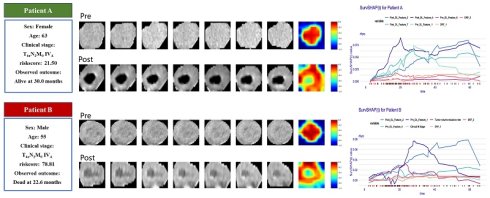

Figure 5 provides some representative patients. Although the two patients were diagnosed at the identical clinical stage, their prognostic outcomes diverged significantly. The model demonstrated a strong ability to make this critical distinction. The Grad-CAM heatmaps indicate that key deep-learning features are extracted from center regions of the tumor. By calculating the SurvSHAP(t) values, the model's prediction results for individual patients were decomposed into the independent contributions of each feature, thereby intuitively illustrating how different features influence OS prediction over time (Figure 5 B-C).

Our study found that assessing patients' prognosis based on the degree of tumor volume regression cannot accurately predict outcomes, which may be related to tumor heterogeneity. Grad-CAM visualizations revealed that key predictive features were primarily concentrated in central tumor regions. By integrating global and local explanation methods, we quantified the contribution of individual features to patient-specific survival predictions, thereby enhancing interpretability. For example, Patients A and B had similar clinical stages but exhibited significantly different risk scores. Patient A, who had a lower risk score of 21.50, alive at 30 months, while Patient B, with a risk score of 78.81, died at 22.6 months. An increasing number of studies are exploring the optimal approaches for maintenance therapy following CCRT in ESCC [26]. Accurate prognostic stratification of patients may help identify those suitable for adjuvant therapy and reduce overtreatment.

Figure 5

(A) Clinical information and Grad-CAM visualizations of representative patients. The darker red areas mean more contribution to prediction. B-C explain the prediction of patients with SurvSHAP(t).